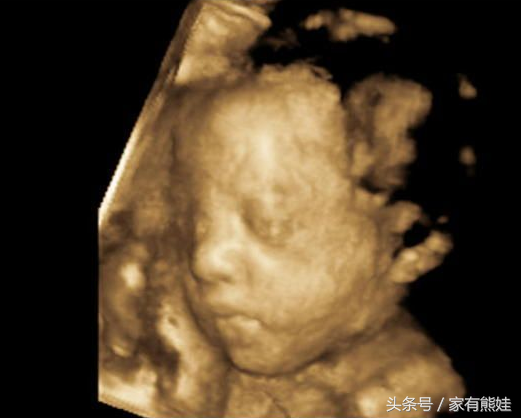

时间过的好快,一下子就37W了,现在好像知道自己肚肚里的是男宝还是女宝,JMM来看过之后猜猜看,也上就要揭晓答案了哦~

孕期特征罗列如下: